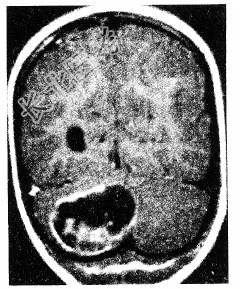

- 单项选择题男性患者,39岁。头痛、步态不稳3个月。查体: 神清,双侧视盘水肿, 右侧轮替动作不能。周围血象红细胞增多,B超发现右肾有一囊性肿物, 头颅CT发现右小脑半球囊性占位性病变(如图所示)。其病变性质最可能是